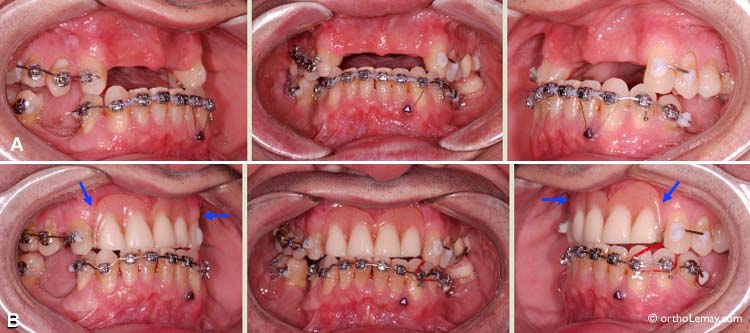

Solutions esthétiques pour dents manquantes pendant l’orthodontie-3

Rétraction de dents antérieures à l’aide de broches linguales iBraces. (A) Condition initiale avec dents antérieures avancées et chevauchées. (B) Une prémolaire a été extraite de chaque côté (flèches bleues) afin de donner l’espace nécessaire pour reculer les dents antérieures. (C) Facettes collées sur les prémolaires (flèches rouges) pour camoufler l’espace d’extraction pendant la rétraction. (D) Après quelques mois, les dents sont partiellement reculées, l’espace d’extraction a diminué et les facettes peuvent être enlevées. Ce cas en cours de traitement n’était pas terminé lors du montage photographique.